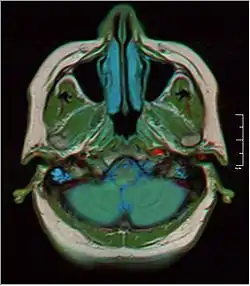

MRI showing fluid in mastoid air cells | |